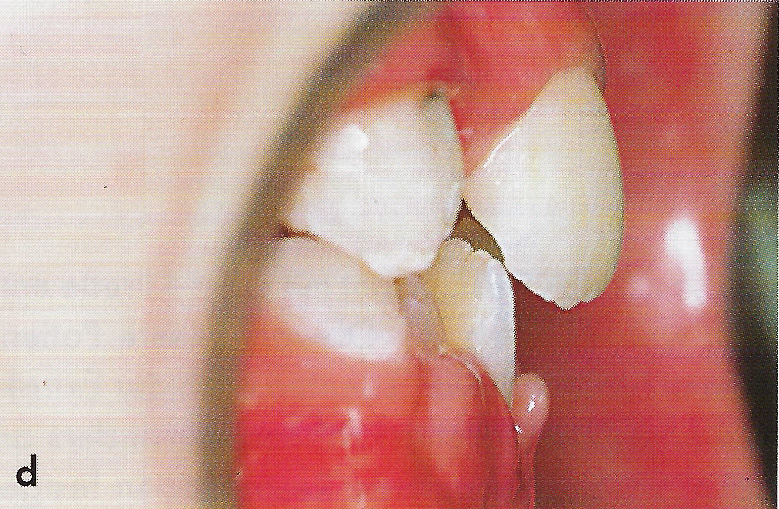

Abb. 1 a bis h Extra- und intraorale Ansicht der Patientin vor Behandlungsbeginn: Kopfbiß beziehungsweise umgekehrter Schneidezahnüberbiß und beidseitiger Kreuzbiß als Folge einer maxillären Hypoplasie sowie hälftenungleicher Mesialbiß infolge mandibulärer Verschiebung nach rechts.

• Ankylose Abb.1d

Diese Patientin war zu Behandlungsbeginn 7 Jahre alt. Sie hatte einen hälftenungleichen Mesialbiß infolge mandibulärer Verschiebung mit Kopfbiß beziehungsweise umgekehrter inzisaler Stufe, rechtsseitigem vollem Kreuzbiß und linksseitigem doppeltem Höckerbiß, maxillärer Kompression sowie Platzmangel in beiden Kiefern (Abb. 1 a bis h). Die kephalometrische Analyse ergab eine progene Kieferlagebeziehung, bedingt durch eine unterentwickelte Maxilla bei vertikalem Gesichtsschädelaufbau.